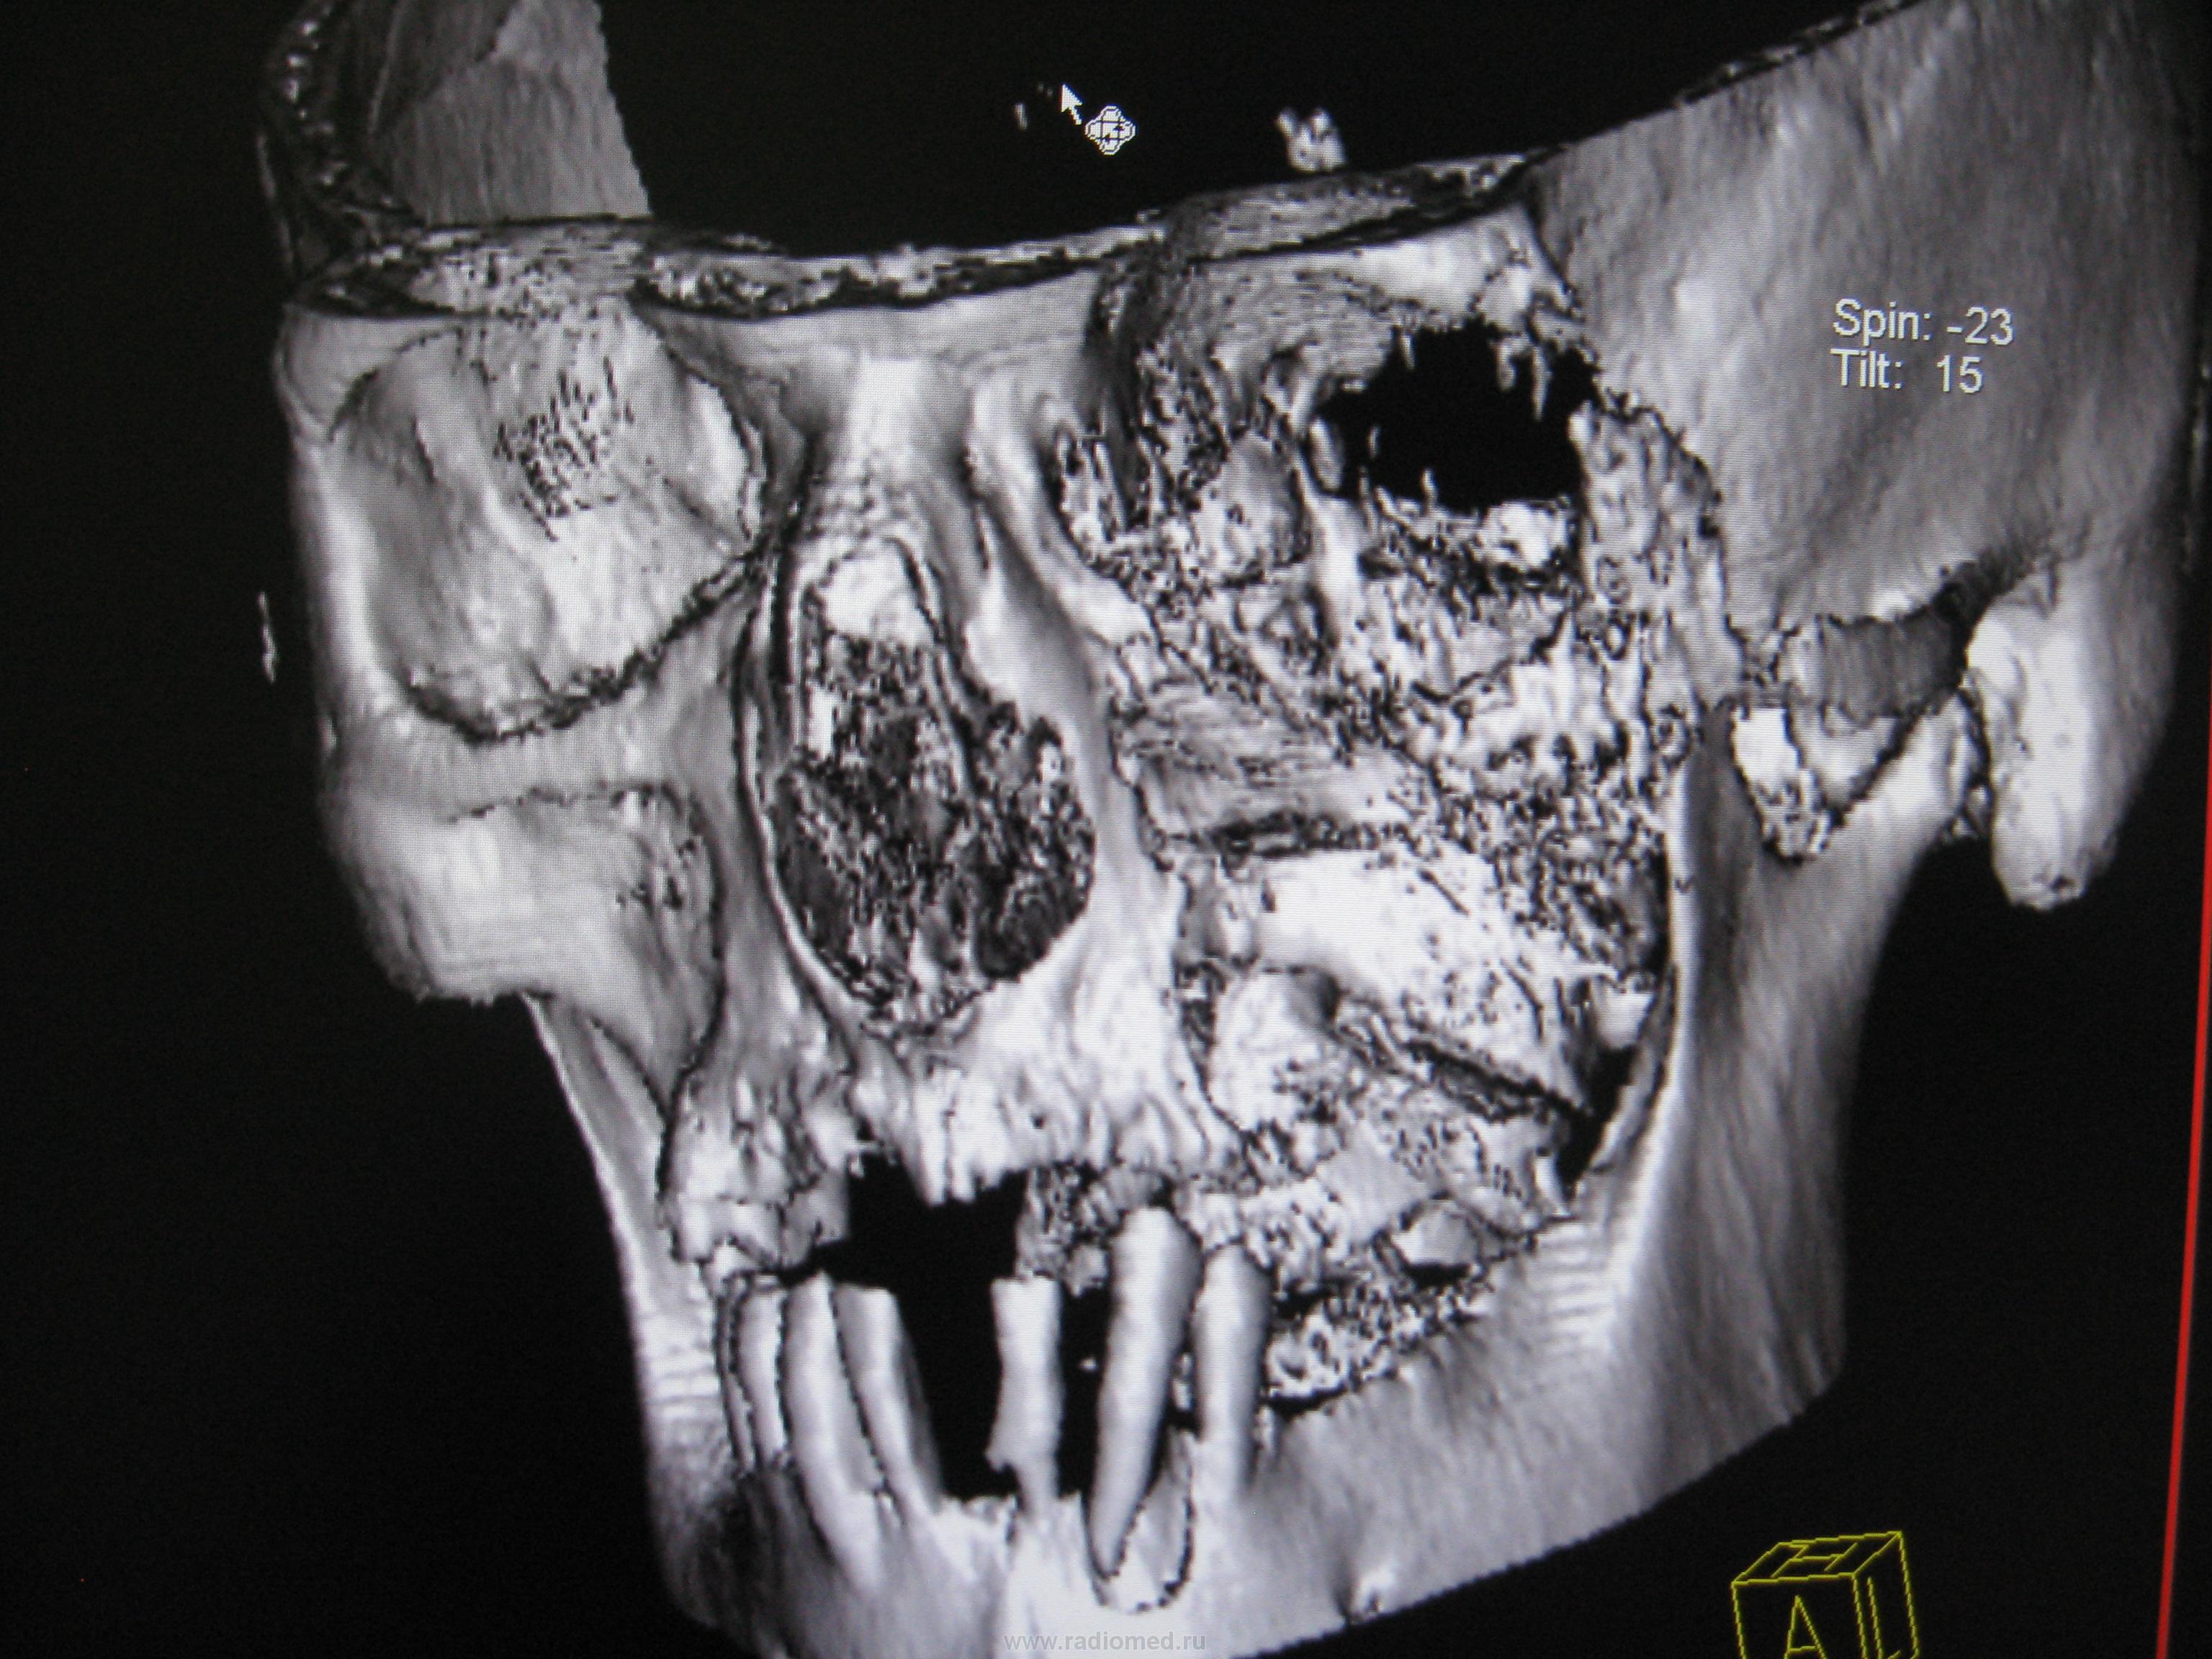

Вот такое безобразие выросло у человека. Когда он обратился образвоание было вероятно меньше к сожалению снимков нет. Лучевая терапия оказалась неэффективной как видите.

Каюсь гистологию даже не смотрел засмотрелся на картинку. Да изначально была гайморова пазуха. Затем после лучевой терапии на фоне ухудшения решили сделать КТ благо сейчас появилась такая возможность. И вот прорастание в глазницу с разрушение нижней её стенки, в носовую, ротовую полости, в среднюю черепную ямку. В общем все бесполезно...

Есть деструкция костей -один из критериев. Гистология в пн. Возраст порядка 50 лет. В пн уточну